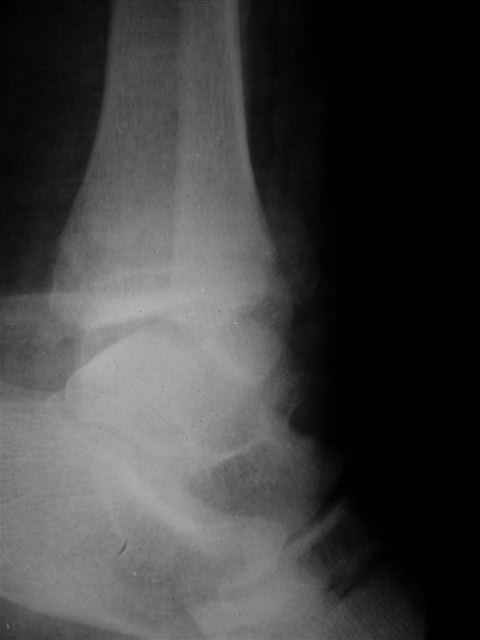

> интересуюсь тактикой лечения повреждений голеностопного сустава.

Ничего сверхъестественного, но если есть интерес, то в понедельник пересниму Рг-граммы и отправлю.

Я предупреждал, что ничего сверхъестественного. Каюсь, что одна из спиц прошла несколько дальше, чем нужно было, но главное - перелом стабилизирован и больной работает суставом в полном объёме, несмотря на представленную раннее травму коленного сустава.